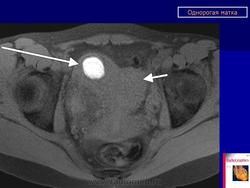

МПС. Женская репродуктивная система. Аномалии и варианты развития. Матка. Однорогая матка. +

Аномалии и варианты развития. Однорогая матка.